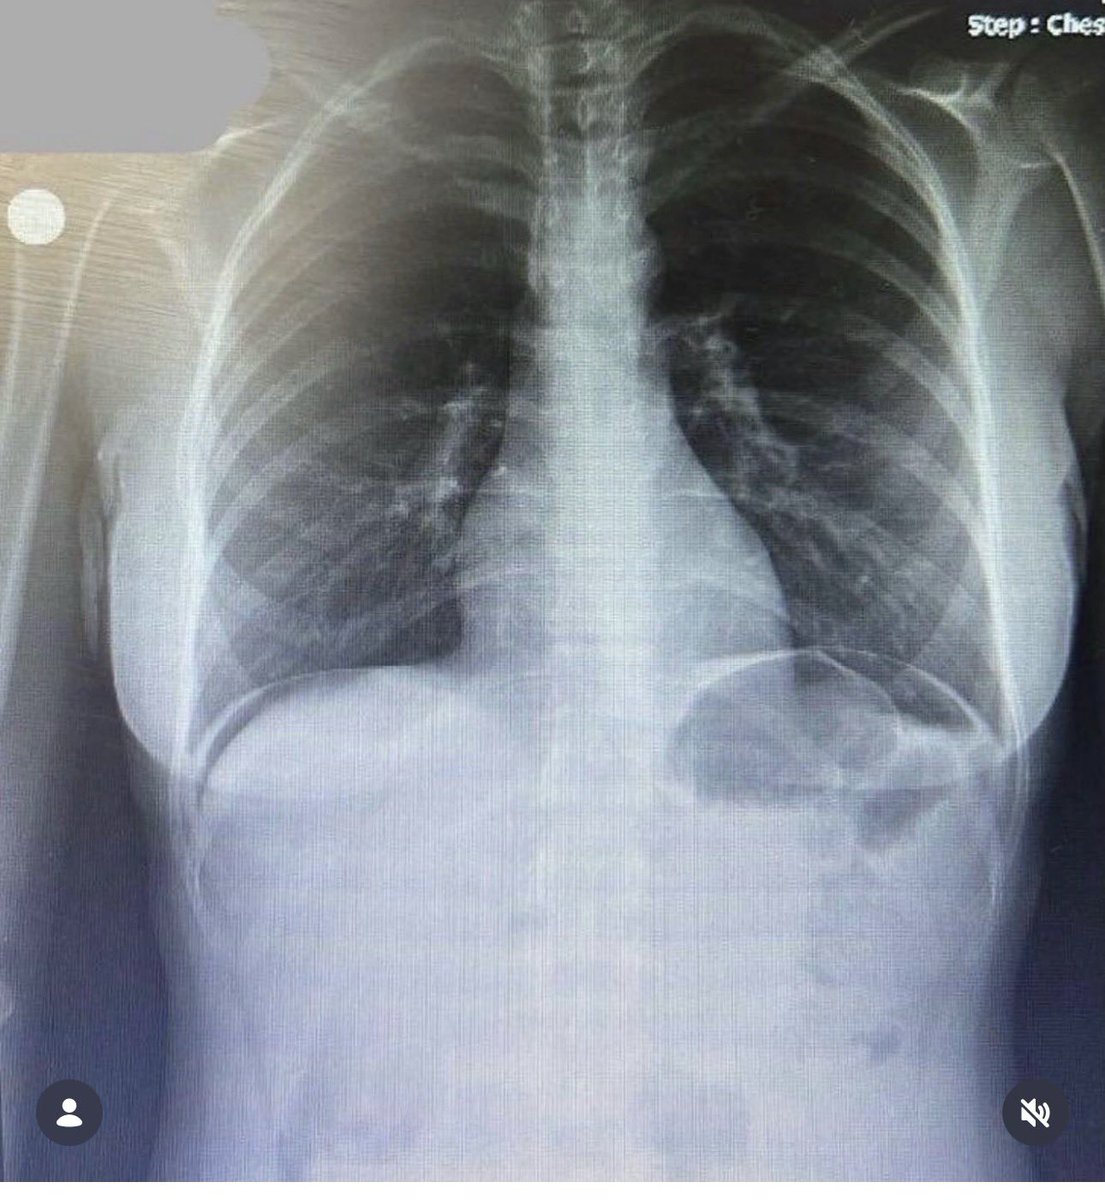

Karın Ağrısı şikayetinde Akciğer grafisi isteme nedenimiz işte budur!!!

Şimdi hastalar ya benim karnım ağrıyor ne alaka akciğer filmi diyecek ama siz siz olun karın ağrısı şikayeti ile başvuran hastalarda Bilirkişi ilk akciğer filmi istemiş mi diye bakıyor! Eğer ki sadece adbg yani karın filmi istenmiş ama akciğer filmi istenmemiş Malpraktis sayılıyor!!! Kanıta dayalı tıp çağındayız gençler! Göğüs ağrısında da PA ac grafisi istemeyi unutmayın! Yani bir PA Ac grafisi bize çok şey anlatır ve malpraktisten korur🥰